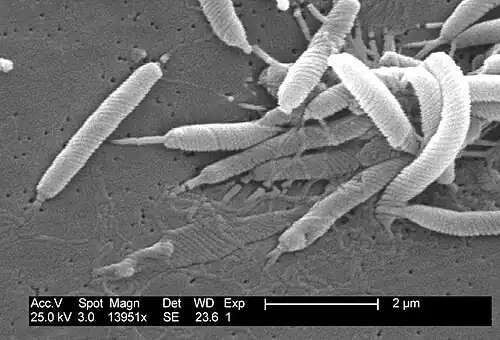

Helicobacter pylori ist ein gramnegatives, mikroaerophiles Stäbchenbakterium, das den menschlichen Magen besiedeln kann. Der spiralig gekrümmte Keim bewegt sich mittels seiner lophotrich angeordneten Geißeln fort.[1] Der Organismus ist vollständig DNA-sequenziert.

Ferner wird auch eine mögliche Übertragung durch Schmeißfliegen diskutiert. Die Besiedlung mit H. pylori erfolgt ausgehend vom Antrum cardiacum der Speiseröhre aboral in Richtung Mageneingang (Kardia) und Magenpförtner (Antrum pyloricum). Hierbei bewegt sich der Keim durch Geißelschlag fort. Spezialisierte Haftstrukturen ermöglichen ihm die besonders feste Anbindung an die Epithelzellen der Magenschleimhaut, die die Voraussetzung für das entzündliche Geschehen darstellt.